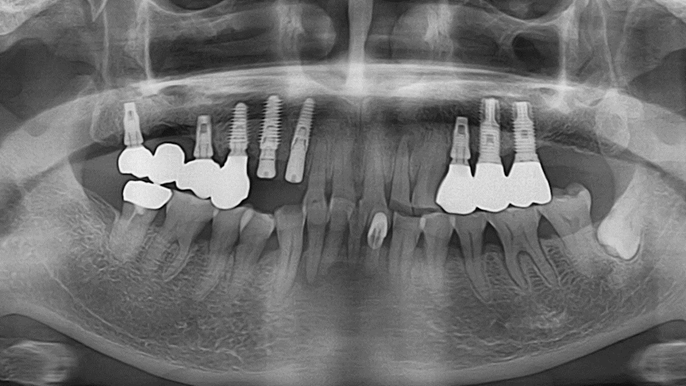

Dr. Sang Tack Lee, edentulous, digital full mouth prosthetics, digital guided surgery, #11, #13, #14, #16, #17, #21, #23, #24, #26, #27, #33, #34, #36, #37, #43, #44, #46, #47, guided surgery, flapless, AnyRidge, R2GATE, Mega ISQ, MEG Torq, MEG Engine, R2GATE Full surgical kit

Dr. Kwang Bum Park, digital guided surgery, bone regeneration, maxillary posterior, #13, #14, guided surgery, GBR, AnyRidge, i-GEN, Mega-Oss, R2GATE, R2GATE Full surgical kit